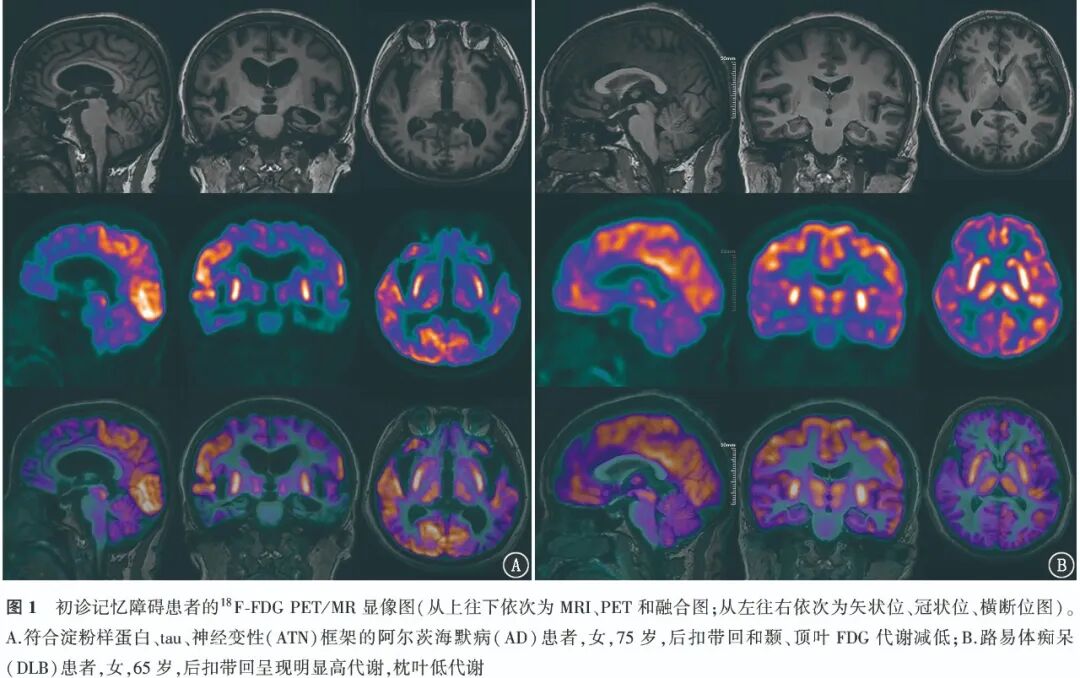

2. Diagnostic Efficacy of 18F-FDG PET for AD Patients.The typical cases of positive visual assessment of 18F-FDG PET are shown in Figure 1. The ROC curve indicates that the AUC for PET-SCORE diagnosing AD is 0.69, with the optimal threshold of 3.20 obtained from the Youden index (0.41). Typical case images of PET-SCORE analysis are shown in Figure 2. The visual assessment of the temporal and parietal lobes had the highest sensitivity for diagnosing AD [91.80% (56/61)], which was statistically significant compared to PET-SCORE (χ2=29.03, P<0.001) and PCC visual assessment (χ2=5.82, P=0.016); the highest specificity was for PET-SCORE [100% (35/35)], which was statistically significant compared to the temporal, parietal lobe visual assessments and PCC visual assessment (χ2 values: 27.03, 14.06, both P<0.001); the highest accuracy was for PCC visual assessment [68.75% (66/96)], exceeding other methods, but the difference was not statistically significant (χ2 values: 0.32, 0.57, 2.12, all P>0.05). The diagnostic efficacy of different parameters for AD is detailed in Table 1.

According to the pattern of reduced FDG uptake, it is closely related to the type of clinical symptoms, thus assisting in the diagnosis and differentiation of AD [12-13]. The typical metabolic pattern of 18F-FDG PET in AD patients includes low metabolism in the temporal and parietal lobes, with the precuneus and PCC often affected [14]. In this study, among 61 AD patients, 56 had reduced metabolism in the temporal and parietal lobes, indicating that this classification standard has high sensitivity (91.80%), but low specificity (17.14%); 47 patients had reduced metabolism in the PCC, with a sensitivity of 77.05% (47/61) and specificity of 54.29% (19/35), with accuracy higher than semi-quantitative parameters (NeuroQ SUVR, PET-SCORE) but no statistically significant difference (all P>0.05). PET-SCORE can be used to assist in diagnosing AD. Previous studies have shown that this parameter has sensitivity for differentiating AD patients from normal controls of 83% and 78%, and specificity of 78% and 94% respectively [15]. Brugnolo et al. [11] compared the statistical parametric mapping (SPM) method and PET-SCORE semi-quantitative parameters for differentiating preclinical AD patients from normal controls, finding that the AUC of the latter (0.87) was higher than that of SPM visual analysis (0.79). Morbelli et al. [15] showed that in differentiating memory impairment-type MCI patients from normal controls, the specificity of PET-SCORE (91.7%) exceeded that of moderately skilled individuals with three years of experience (79.8%). In this study, to better fit the clinical practice scenario, differentiation was made between AD and non-AD patients rather than normal individuals, resulting in a lower sensitivity for PET-SCORE (40.98%), but with high specificity (100%), consistent with previous studies.